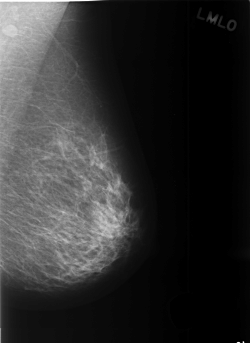

C_0374_1.LEFT_MLO

C_0374_1.LEFT_CC

LEFT_MLO LINES 5480 PIXELS_PER_LINE 4000 BITS_PER_PIXEL 12 RESOLUTION 50 NON_OVERLAY

LEFT_CC LINES 5808 PIXELS_PER_LINE 3880 BITS_PER_PIXEL 12 RESOLUTION 50 NON_OVERLAY